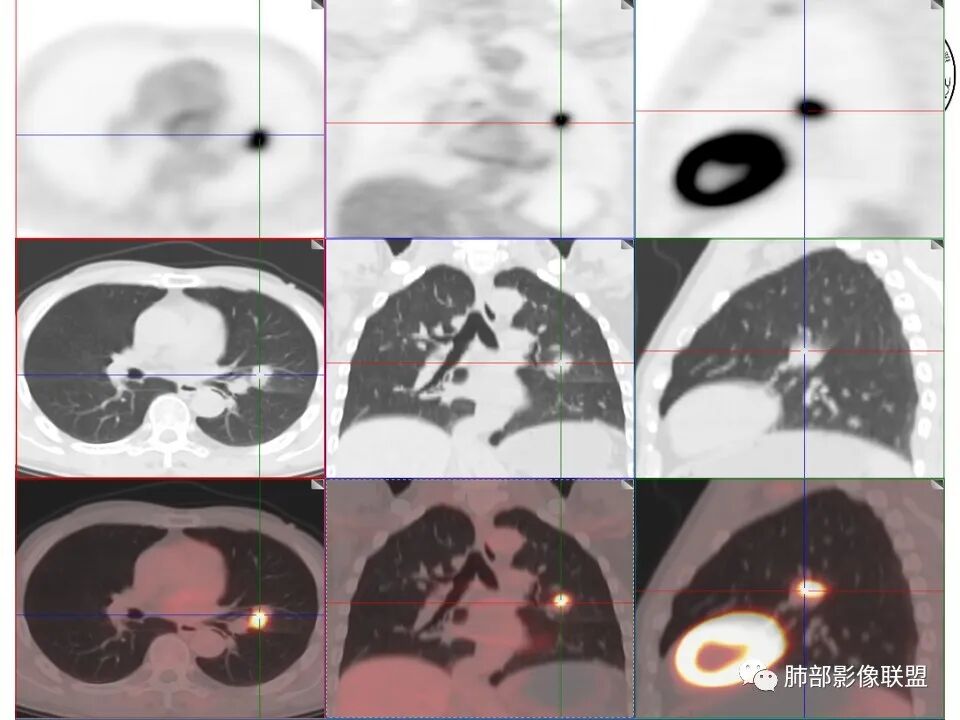

小兜: 晨读:一月前全身乏力就诊,CT示左肺上叶舌段近肺门及叶间胸膜结节,边缘不规则伴少量磨玻璃密度,与叶间胸膜相贴,叶间胸膜局部增厚伴略彭隆,未见明显牵拉。PET/CT代谢增高,SUVMax=9.8。综合考虑为炎性肉芽肿性病变,肺癌代排

丁云: 肺部联盟晨读病例:左肺上叶舌段不规则结节,有平直凹陷及膨隆,相邻血管穿行,支气管截断,血管贴边,胸膜增厚,PET高摄取,但也不是很高。首先考虑炎性肉芽肿。鉴别腺癌。

年龄不详,推测中老年人,因全身乏力就诊,CT发现左肺上叶结节灶,无明显咳嗽、发热等症状,无吸烟病史,配偶曾患“肺结核”,化验检查痰结核菌涂片阴性,CYFR轻度升高,PET-CT局部高摄取。

左肺上叶舌段近肺门区不规则结节,密度较均匀,结节边缘平直为主,可见粗短毛刺、毛刺偏软,浅分叶,收缩力不强,膨隆也不明显,周围可见模糊GGO,病灶内部支气管显示不清,病变远端支气管明显扩张,病灶与叶间裂呈宽基底相连,见刀切征,并见叶间裂多发结节影,叶间裂未见明显移位。

患者推测中老年人,无明显临床症状,肺气肿背景不明显,虽然病灶整体炎性征象较多,叶间胸膜多发结节,常规要考虑结核和腺癌,PET-CT肿瘤和炎性病变都可以高摄取,敏感性高,但特异性不高,而且腺癌周围缺乏清晰的磨玻璃及收缩力不强,故暂不考虑;虽然左肺上叶舌段病灶与支气管关系密切,如果周围磨玻璃推测为早期的阻塞性炎症,还有CYFR轻度升高,鳞癌不能除外,但是病灶的整体形态比较符合炎性改变。本病例可惜未行CT增强扫描,无法观察结节的强化特点及病灶内血管走行情况。